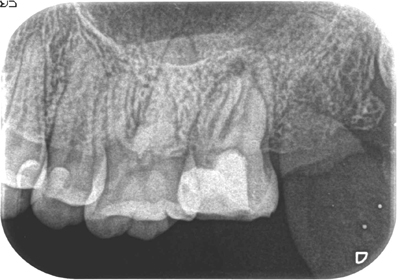

症例5【50代男性】前歯4本の根尖病巣

治療前

治療後(24ヶ月後)